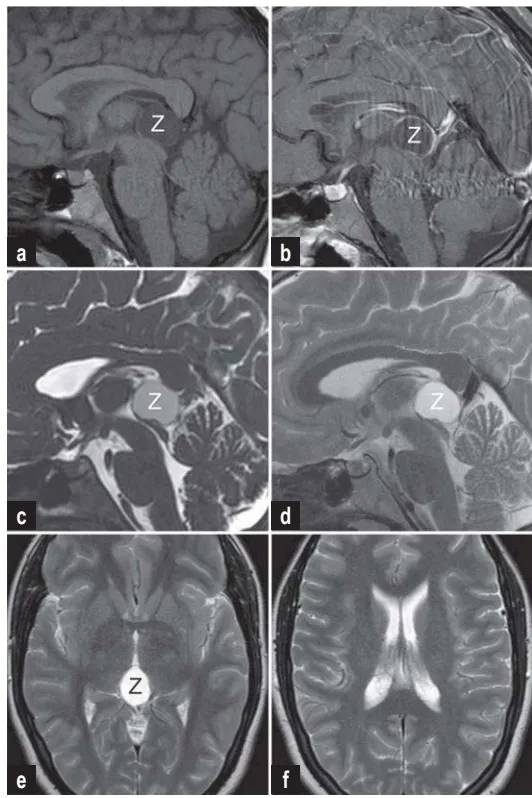

影像学检查显示:矢状位CISS序列可见导水管入口明显狭窄,IRTSE序列显示导水管内脑脊液流动正常,术前T2加权像显示侧脑室宽度正常,术后影像确认囊肿完全切除。

MRI检查中,松果体囊肿典型表现为球形结构,T1加权像呈低信号,增强扫描可见边缘强化。最佳诊断序列组合包括T1加权、CISS序列和流动敏感序列,可全面评估囊肿与导水管的空间关系。

MRI诊断标准包括:

T1加权像显示类圆形低信号病灶伴边缘环形强化

CISS序列清晰显示囊肿与中脑导水管的关系

T2加权像测量脑室宽度,排除脑积水

流动敏感序列评估脑脊液动力学状态

诊断重点并非囊肿绝对尺寸,而是其对关键结构的压迫程度,特别是导水管受累情况。